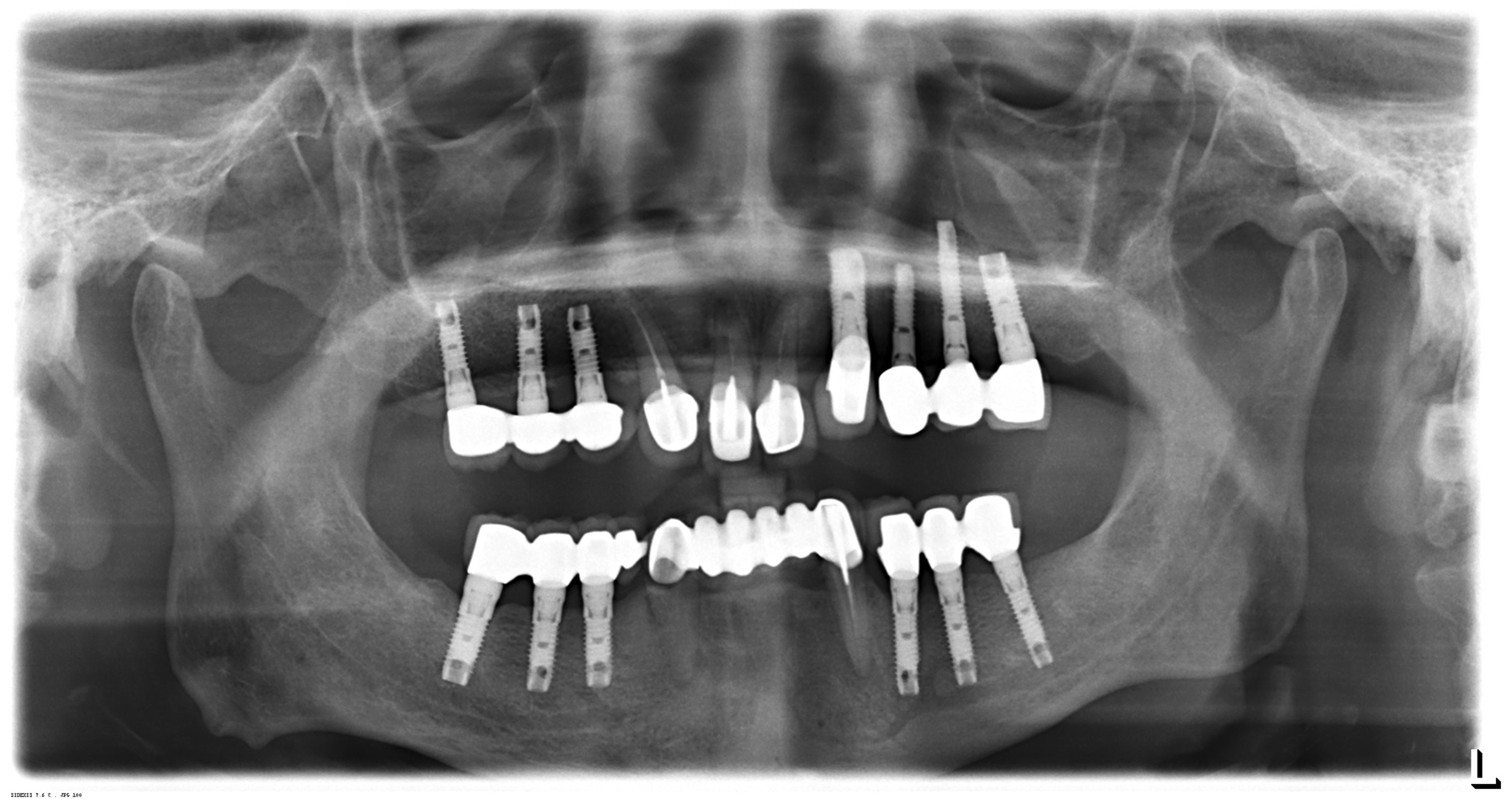

植牙案例

植牙可以用多久?這個案例給你答案

陳先生今年63歲,早期做牙橋越做越長,一顆壞掉後就只能整排拿掉,

20年前經由朋友介紹到光田醫院給宋主任做植牙,一直都很照醫囑回診,而且吃完東西後一定刷牙及牙間刷使用。到現在回診,每一根植體都還是健康穩定!